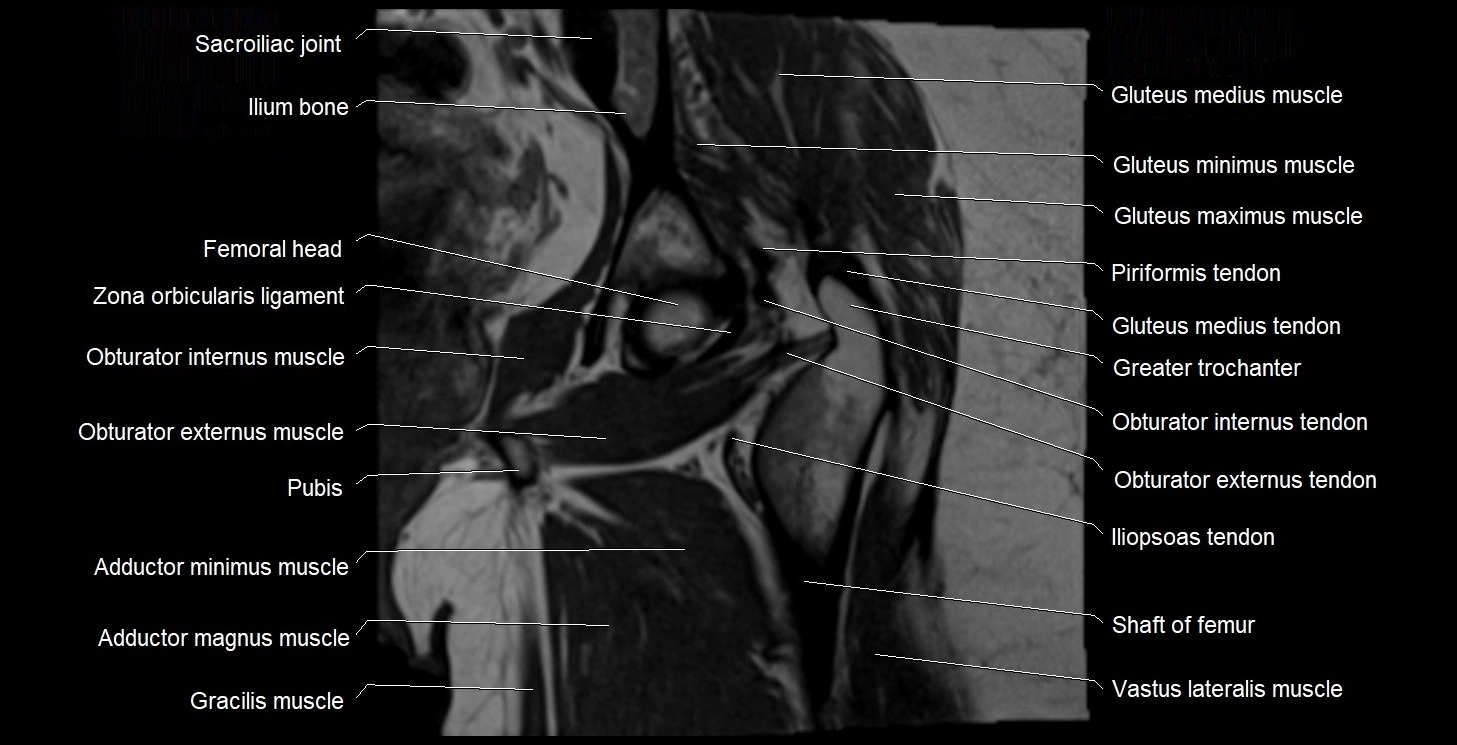

- Adductor brevis muscle

- Adductor magnus muscle

- Adductor minimus muscle

- Gluteus maximus muscle

- Gluteus medius muscle

- Gluteus medius tendon

- Gluteus minimus muscle

- Greater trochanter

- Head of femur

- Iliopsoas tendon

- Ilium bone

- Ischial tuberosity

- Ischium bone

- Obturator externus muscle

- Obturator externus tendon

- Obturator internus muscle

- Obturator internus tendon

- Sacroiliac joint

- Vastus lateralis muscle